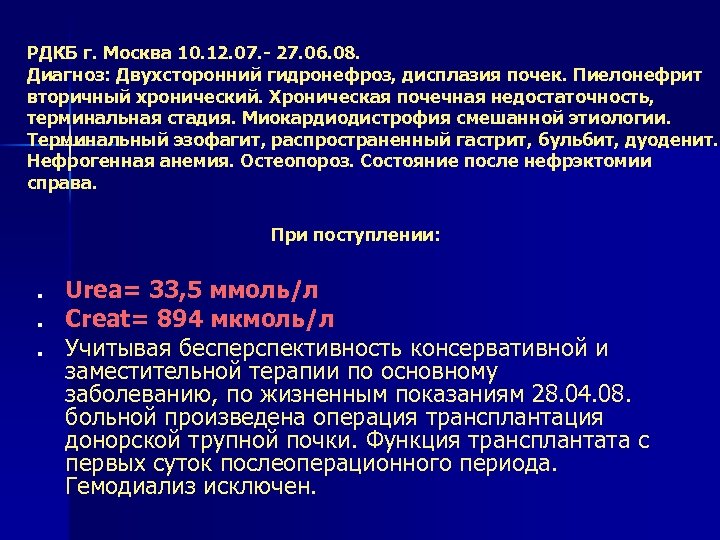

РДКБ г. Москва 10. 12. 07. - 27. 06. 08. Диагноз: Двухсторонний гидронефроз, дисплазия почек. Пиелонефрит вторичный хронический. Хроническая почечная недостаточность, терминальная стадия. Миокардиодистрофия смешанной этиологии. Терминальный эзофагит, распространенный гастрит, бульбит, дуоденит. Нефрогенная анемия. Остеопороз. Состояние после нефрэктомии справа. При поступлении: n n n Urea= 33, 5 ммоль/л Creat= 894 мкмоль/л Учитывая бесперспективность консервативной и заместительной терапии по основному заболеванию, по жизненным показаниям 28. 04. 08. больной произведена операция трансплантация донорской трупной почки. Функция трансплантата с первых суток послеоперационного периода. Гемодиализ исключен.

РДКБ г. Москва 10. 12. 07. - 27. 06. 08. Диагноз: Двухсторонний гидронефроз, дисплазия почек. Пиелонефрит вторичный хронический. Хроническая почечная недостаточность, терминальная стадия. Миокардиодистрофия смешанной этиологии. Терминальный эзофагит, распространенный гастрит, бульбит, дуоденит. Нефрогенная анемия. Остеопороз. Состояние после нефрэктомии справа. При поступлении: n n n Urea= 33, 5 ммоль/л Creat= 894 мкмоль/л Учитывая бесперспективность консервативной и заместительной терапии по основному заболеванию, по жизненным показаниям 28. 04. 08. больной произведена операция трансплантация донорской трупной почки. Функция трансплантата с первых суток послеоперационного периода. Гемодиализ исключен.